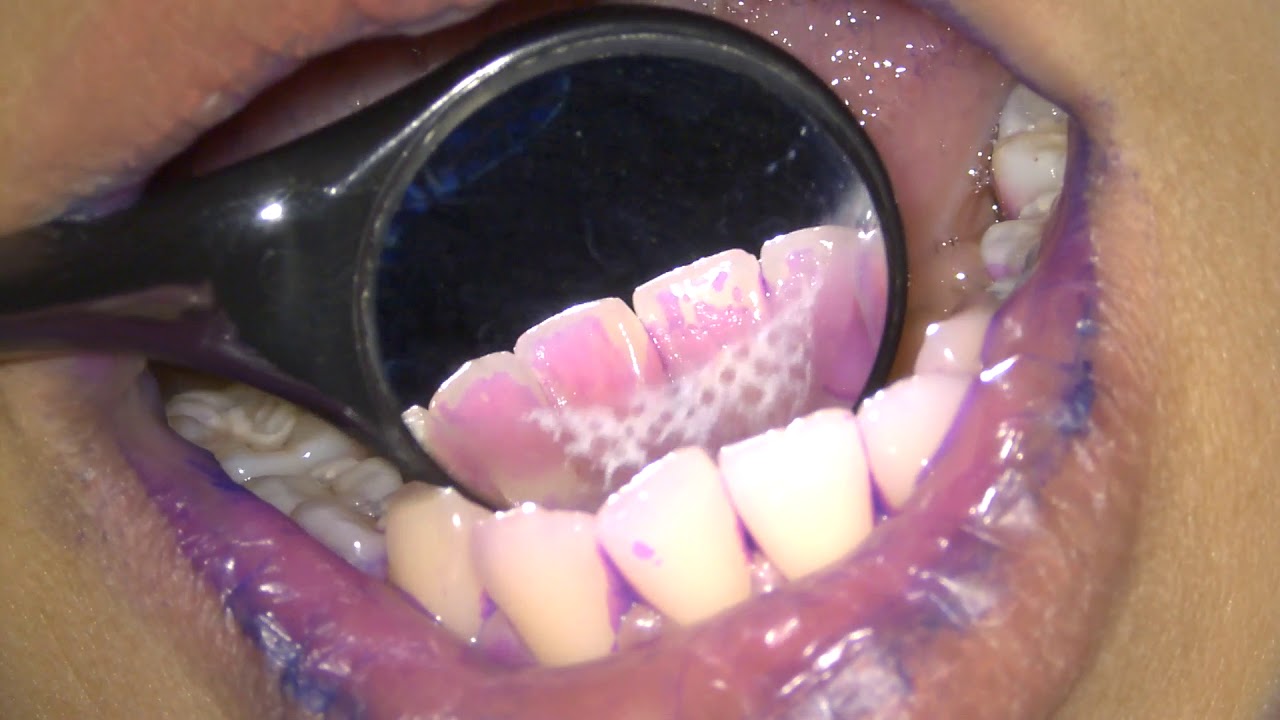

Plaque Index For Teeth Repeated determination of an index during the course of preventive or active therapy can help ascertain the degree of patient motivation compliance and treatment success or failure. The plaque control record by o'leary is a very simple teaching method to help you improve on your daily oral hygiene of brushing and flossing. this was developed by dr. timothy j. o'leary.

Gingival And Plaque Index Pdf It explains that the o'leary index measures the percentage of tooth surfaces with plaque, while the copd and ceod indices count the number of permanent and temporary teeth, respectively, that are decayed, lost, or filled. Index scores pre examination and pre scoring through o’leary method. experimental group was ocialized through video and study model, and was instructed to brush teeth two times a day for seven days: after having breakfast and before sleeping, whereas control group was not socialized and instructed. Summarized measurements of the o'leary plaque index. [ ] objective: to compare the efficacy of dental plaque removal between manual and powered toothbrushes in individuals with syndactyly . Detection and quantification of bacterial dental plaque is considered to be crucial in dental practice. the o'leary index is a simple tool to measure the amount of bacterial dental plaque on teeth and one of the most effective means to evaluate oral hygiene.

Oral Hygine Index And Oral Hygiene Index Simplified Pdf Summarized measurements of the o'leary plaque index. [ ] objective: to compare the efficacy of dental plaque removal between manual and powered toothbrushes in individuals with syndactyly . Detection and quantification of bacterial dental plaque is considered to be crucial in dental practice. the o'leary index is a simple tool to measure the amount of bacterial dental plaque on teeth and one of the most effective means to evaluate oral hygiene. By incorporating the o’leary index into our pipeline, we also provided a clinically interpretable measure of plaque severity. this index aggregated the detected plaque into mild, moderate, or severe categories, aligning our automated analysis with a standard dental plaque scoring system. The plaque control record (o'leary index) appears to be a commonly used oral hygiene index for assessing oral health skills. this index provides sufficient information for patient education; however, the time involved in data collection reduces its value. The o'leary index consisted of recording the presence or ab sence of disclosed plaque on the mesial, distal, buccal and lin gual surfaces of all teeth. the percentage of disclosed plaque was then calculated for each participant. O'leary plaque control record overview the plaque control record was developed as a simple method for clinicians to record the presence of plaque on individual tooth surfaces at initial and follow up appointments. it allows the clinician and patient to visualize progress in plaque control.

Oral Hygine Index And Oral Hygiene Index Simplified Pdf By incorporating the o’leary index into our pipeline, we also provided a clinically interpretable measure of plaque severity. this index aggregated the detected plaque into mild, moderate, or severe categories, aligning our automated analysis with a standard dental plaque scoring system. The plaque control record (o'leary index) appears to be a commonly used oral hygiene index for assessing oral health skills. this index provides sufficient information for patient education; however, the time involved in data collection reduces its value. The o'leary index consisted of recording the presence or ab sence of disclosed plaque on the mesial, distal, buccal and lin gual surfaces of all teeth. the percentage of disclosed plaque was then calculated for each participant. O'leary plaque control record overview the plaque control record was developed as a simple method for clinicians to record the presence of plaque on individual tooth surfaces at initial and follow up appointments. it allows the clinician and patient to visualize progress in plaque control.